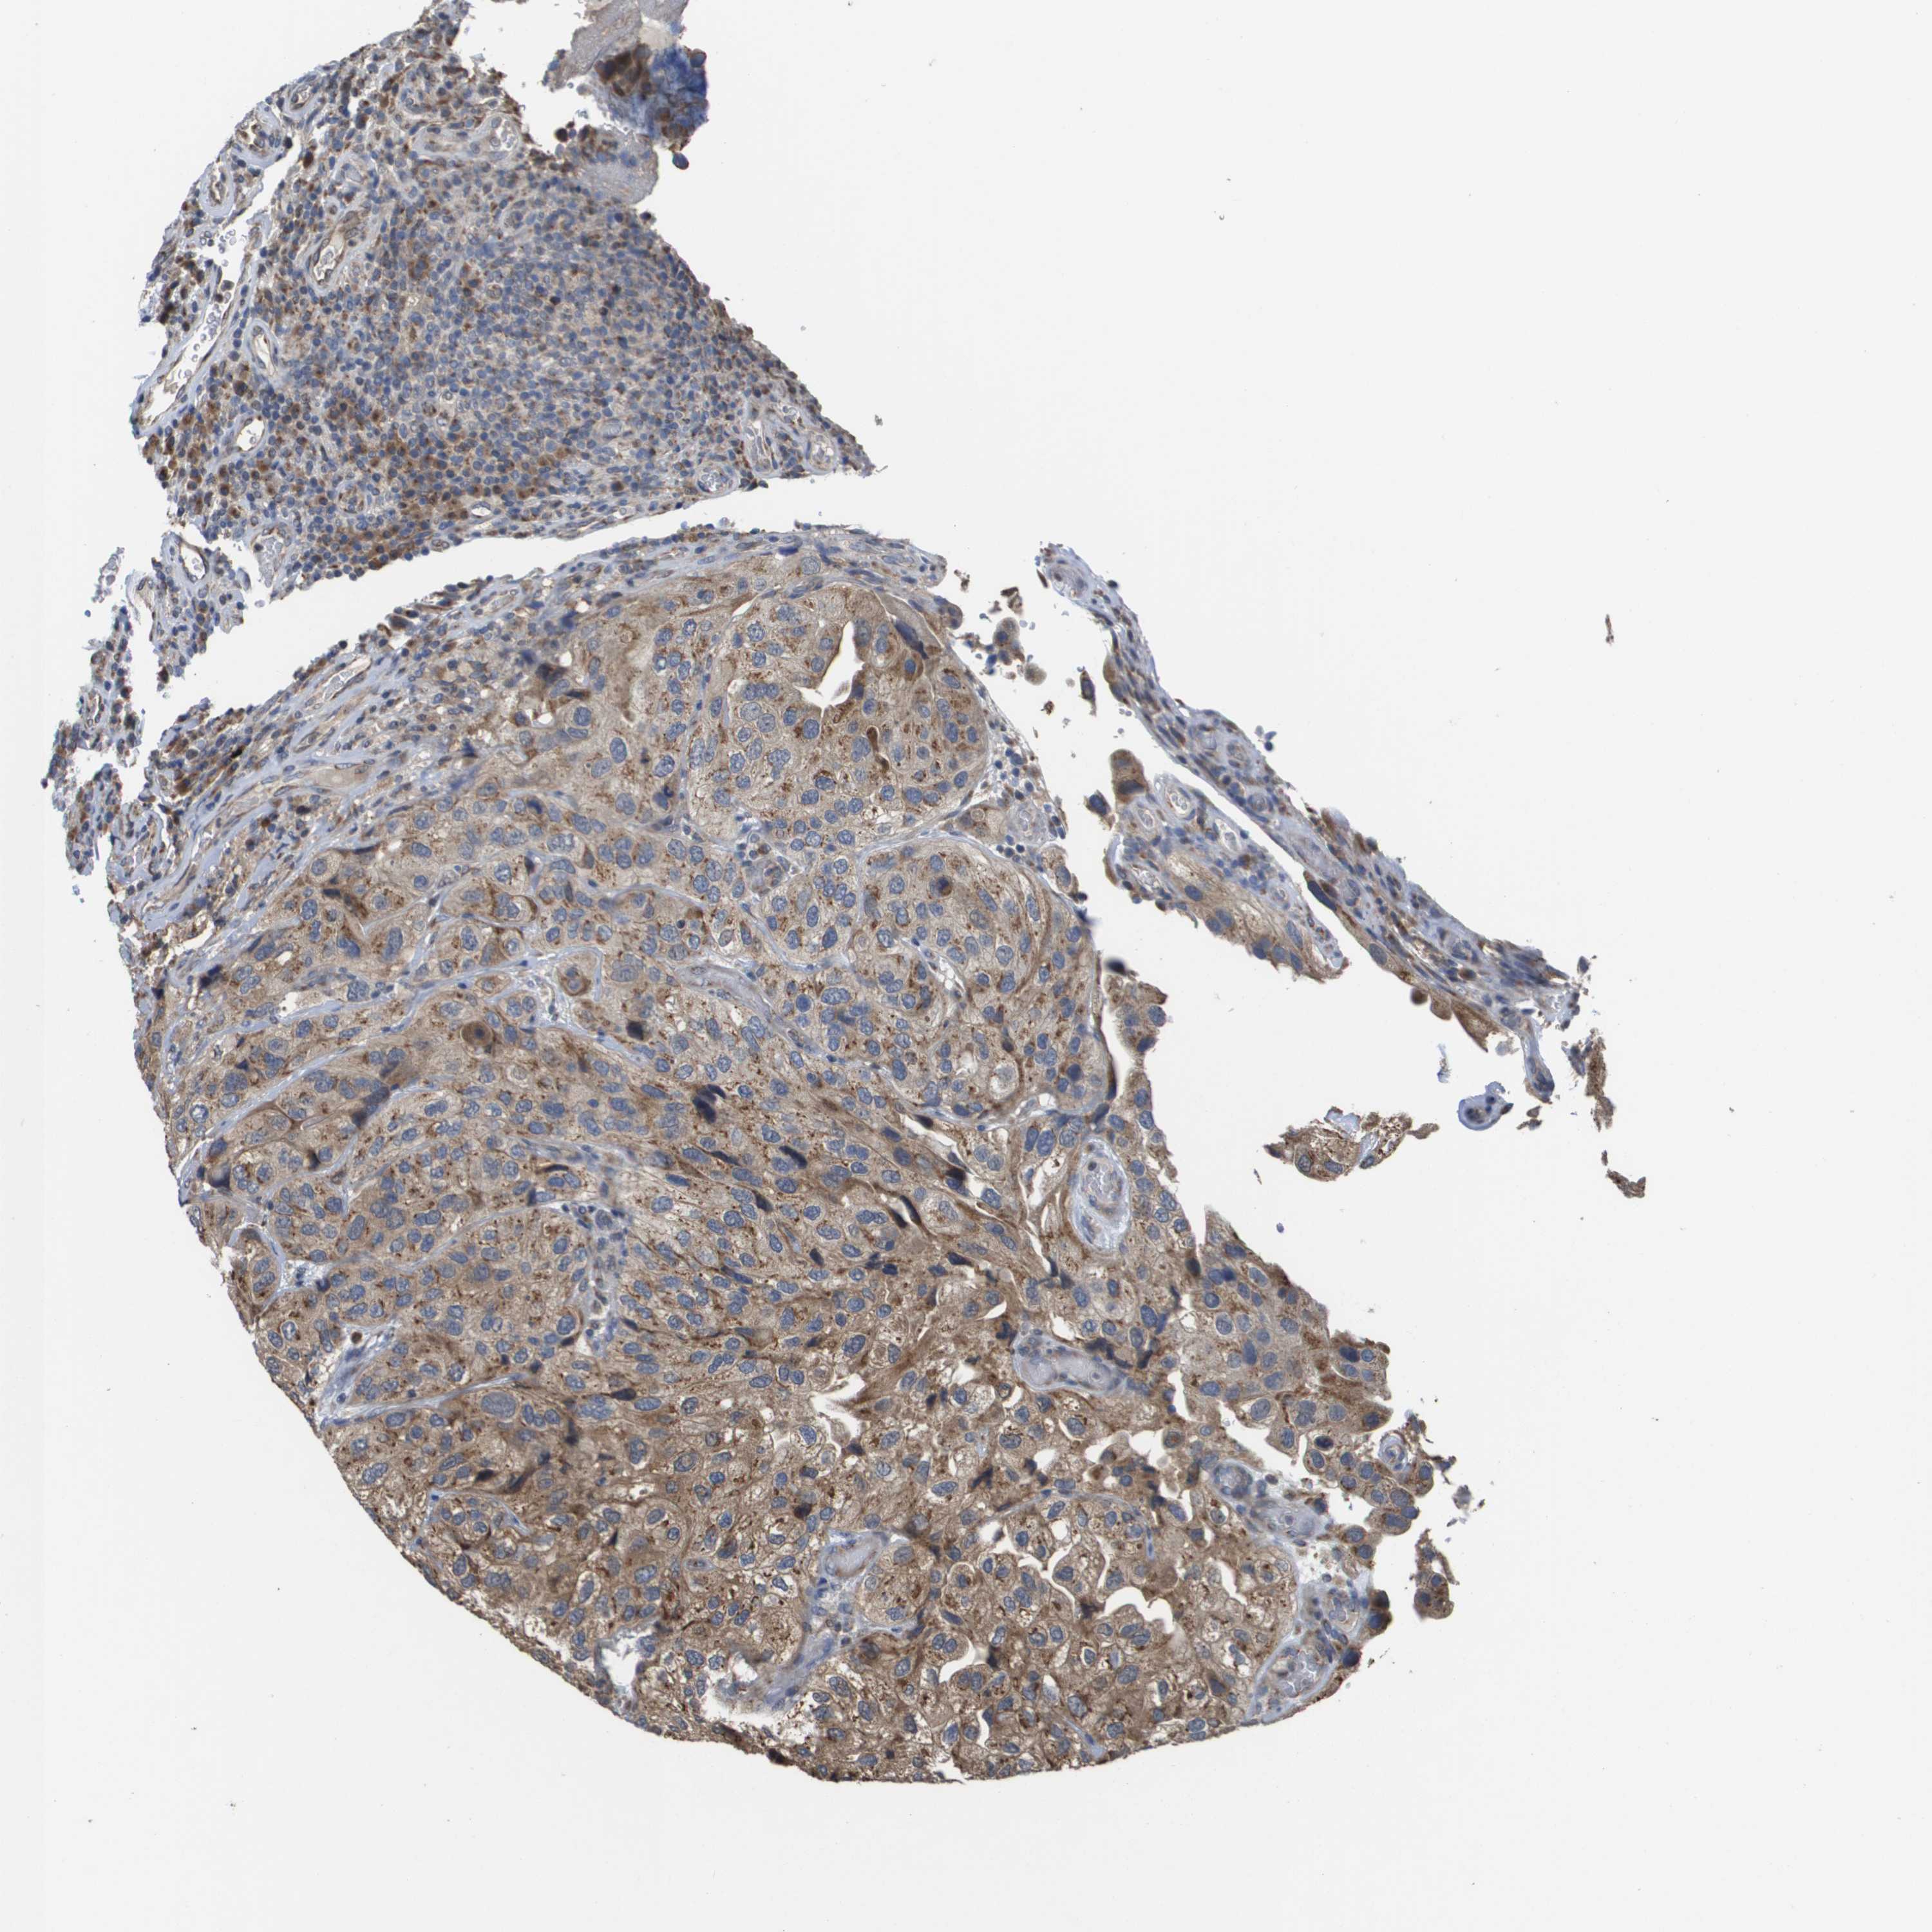

UROTHELIAL CANCER - Protein expressioni

A mouse-over function shows sample information and annotation data. Click on an image to view it in a full screen mode. Samples can be filtered based on level of antibody staining by selecting one or several of the following categories: high, medium, low and not detected. The assay and annotation is described here.

Note that samples used for immunohistochemistry by the Human Protein Atlas do not correspond to samples in the TCGA dataset.

Antibody stainingi

Antibody staining in the annotated cell types in the current human tissue is reported as not detected, low, medium, or high, based on conventional immunohistochemistry profiling in selected tissues. This score is based on the combination of the staining intensity and fraction of stained cells.

Each image is clickable and will lead to virtual microscopy that enables deeper exploration of all samples and also displays staining intensity scores, fraction scores and subcellular localization as well as patient and tissue information for each sample.

Antibody HPA006277

Antibody HPA006507

Antibody CAB017027

Staining

High

Medium

Low

Not detected

Intensity

Strong

Moderate

Weak

Negative

Quantity

>75%

75%-25%

<25%

None

Location

Nuclear

Cytoplasmic/membranous

Cytoplasmic/membranous,nuclear

Urothelial carcinoma, Low grade

Urothelial carcinoma, High grade